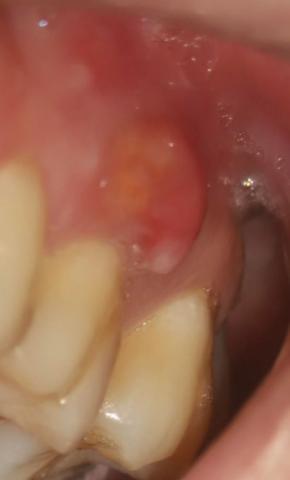

This intra-oral image shows a large, red, swollen lesion on the gum tissue adjacent to a posterior tooth. The appearance is consistent with an active localized gum infection, likely involving deeper periodontal tissues and possibly the underlying bone if not treated promptly.

Prominent red, dome-shaped swelling on gingiva

Inflamed, shiny soft tissue

Adjacent tooth shows plaque accumulation near the gum margin

No visible drainage at the time of imaging

Localized gingival or periodontal abscess

Acute gum infection adjacent to posterior tooth

Possible early spread toward supporting bone